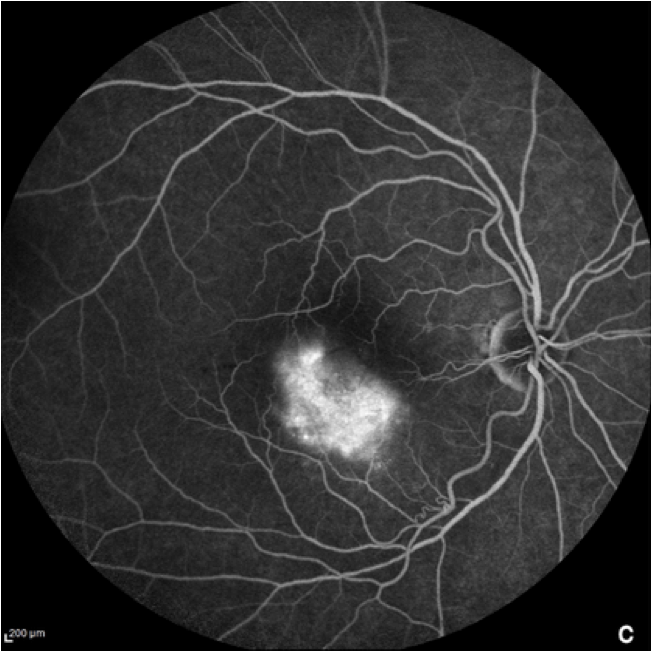

Autofluorescencia del fondo de ojo

La autofluorescencia del fondo de ojo es una importante técnica de imagen para el diagnóstico y monitorización de la DMAE, en particular de la DMAE avanzada seca o atrofia geográfica (AG).11 Se utiliza una luz específica (normalmente azul) para producir la autofluorescencia de una molécula llamada lipofuscina, que suele estar distribuida uniformemente por toda la retina.8 Las regiones no sanas de la retina pueden aparecer más oscuras en el caso de las zonas atróficas, o más brillantes en el caso de las drusas, ambos signos de DMAE.8,13 Elpatrón de fluorescencia puede indicar la potencial tasa de progresión de la DMAE de un paciente.14